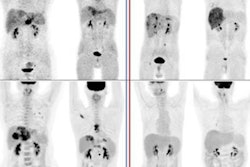

French researchers looked at how patients with hepatocellular carcinoma (HCC) responded to TARE on PET/CT imaging early after treatment using either FDG or an experimental radiotracer called F-18 fluorocholine (FCH). Early PET/CT with either tracer could predict early responses to treatment, as well as patients' overall survival, they found.

Of the 37 patients, 15 (41%) exhibited an early post-treatment PET/CT response based on imaging with at least one of the two tracers, the researchers found. A response at one month (based on mRECIST) was observed in 10 (29%) of 35 patients. Twelve (52%) of 23 patients exhibited an mRECIST response at six months.

A 74-year-old man with known liver cirrhosis. The patient underwent multiphase contrast-enhanced CT. A lesion in the liver dose (arrow) shows hyperenhancement in the arterial phase (A) and washout in the delayed phase (not shown), consistent with hepatocellular carcinoma. The lesion also shows marked hypermetabolism on FDG-PET/CT (B) but not on F-18 FCH PET/CT (C). The patient underwent multiphase contrast-enhanced CT and FDG-PET/CT one month after radioembolization. The lesion was stable in size and demonstrated persistent hyperenhancement in the arterial phase (D) and washout in the delayed phase (E) but a complete response on FDG-PET/CT (F). The patient underwent MRI six months after the procedure. The lesion shows complete response according to mRECIST, including hyperintensity on unenhanced fat-suppressed T1-weighted imaging (G), without internal enhancement on the subtracted arterial-phase image (H). Image courtesy of the American Journal of Roentgenology.Early PET/CT response was significantly associated with prolonged overall survival on univariable (hazard ratio = 0.37) and multivariable analyses (hazard ratio = 0.24), the group found.

"Our study suggests that early post-TARE evaluation by PET/CT using FDG or [F-18 FCH] may predict six-month response and [overall survival] in patients with HCC," the authors wrote.